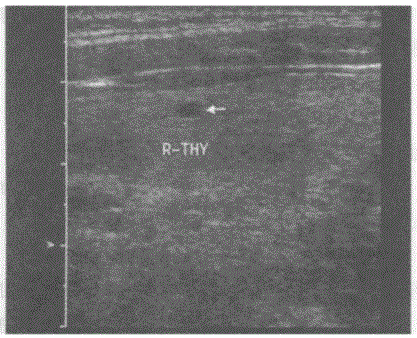

问题 临床资料:女,45岁,自述发现左颈部包块1年余。 超声综合描述:甲状腺右叶形态大小正常,内可见数个低回声区(箭头所示),无包膜,内回声尚均匀;左叶增大失常态,内可见6.9cm×4.0cm中等回声,边界清晰,内回声不均,中部可见3.5cm×1.8cm不规则无回声区,CDFI:双侧甲状腺内血流信号不丰富,低回声区内可见少许血流信号。 超声提示:

选项 A.甲状腺腺瘤 B.毒性甲状腺肿(原发性甲状腺功能亢进) C.结节性甲状腺肿并囊性变 D.甲状腺正常声像图

答案 C